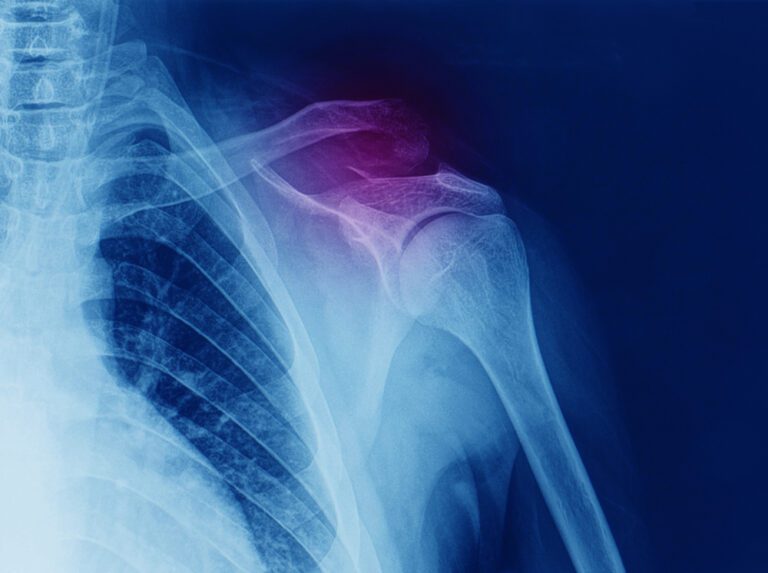

A articulação acromioclavicular está localizada na parte superior do ombro, mais precisamente entre dois ossos da cintura escapular, a clavícula e o acrômio, um osso da escápula. Como as articulações do ombro são as que mais permitem a realização de movimentos no corpo humano, elas estão sujeitas a lesões e algumas condições que podem causar dor e limitação dos movimentos na região, como artrose, osteólise e luxação acromioclavicular.

Por fim, pode ocorrer também a luxação acromioclavicular, uma lesão que acomete os ligamentos que estabilizam a articulação. A luxação acontece por conta de traumas na parte de trás do ombro quando há uma queda sobre o local, causando dores e edema na lateral do ombro. A condição pode ser diagnosticada por meio de exames físicos e exames de imagem, como raio-X e ultrassonografia.